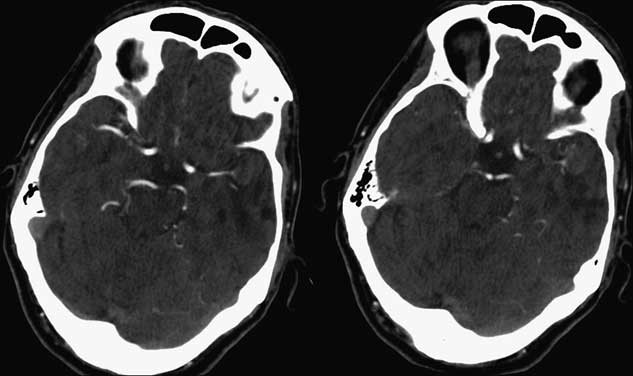

The patient had an uncomplicated hospital stay in the neurosurgical ward, was started on acetylsalicylic acid and clopidogrel, and was eventually transferred to the stroke rehabilitation unit. Prolonged Holter monitor demonstrated no evidence of arrhythmia, an Echocardiogram showed no intracardiac abnormality, and carotid CT Angiogram (CTA) showed no significant stenosis. Follow-up CTA performed 2 and 9 months post-stroke showed no intra-aneurysmal flow and no change in the morphology of the aneurysm dome, wall or thrombus. Partial recanalization of the M1 segment was seen at the MCA bifurcation, though with persistent attenuation of distal MCA branches (Figure 3). Therefore continued surveillance with serial neuroimaging and clinical follow-up is planned.

Figure 3 Follow-up CT Angiogram 11 weeks post-stroke demonstrating unchanged aneurysmal geometry and intensity, with partial recanalization of a distal M2 segment.